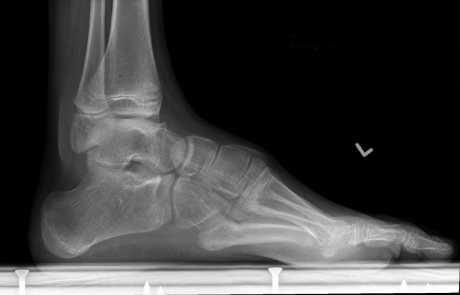

Stres frakture

Kod sportaša, stres frakture najčešće se događaju na donjim ekstremitetima i to redom na kostima stopala i potkoljenice te rijetko na natkoljenici i zdjelici

Bol zbog kalcifikata u peti

Osim samog aktivnog liječenja, nužno je provjeriti obuću te izbjegavati tvrde i uske cipele, a preferirati meku obuću poput sportske